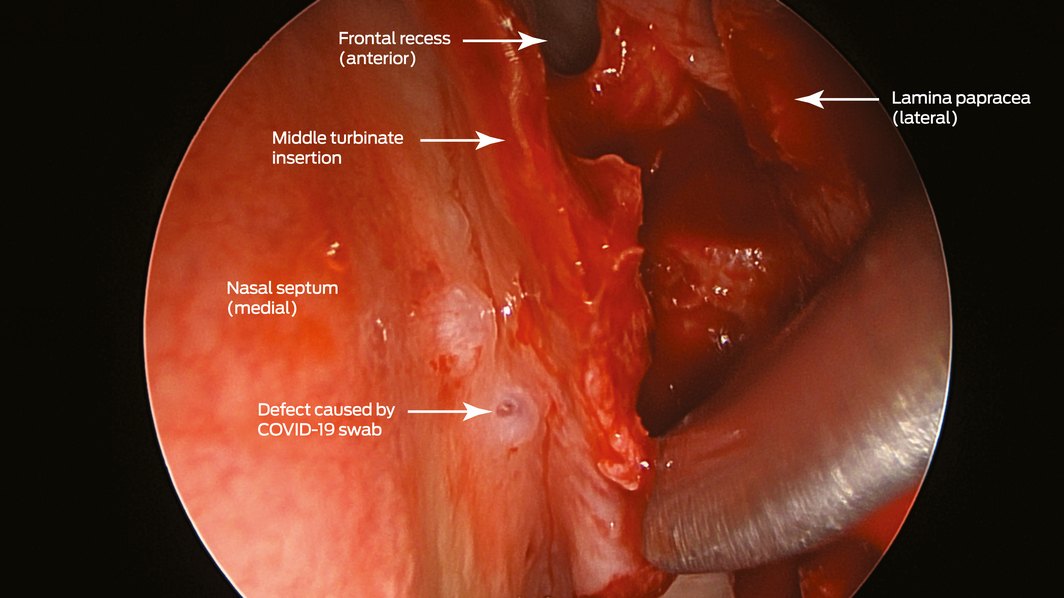

Box 2 – Endoscopic view (45° endoscope) of the defect created by the coronavirus disease 2019 (COVID‐19) swab (left nasal cavity)

A 67‐year‐old woman was referred to our ear, nose and throat department with confirmed cerebrospinal fluid (CSF) rhinorrhoea. She was recently treated for proven bacterial meningitis, having presented to a regional hospital with headache, nausea and photophobia 2 months previously. The patient precisely recalled the onset of unilateral clear rhinorrhoea, which occurred within hours of an “extremely painful” coronavirus disease 2019 (COVID‐19) swab test. This occurred approximately 48 hours prior to presentation to the emergency department. She had no other historical or medical risk factors for a CSF fistula (eg, previous surgery, trauma) nor harboured any stigmata of idiopathic intracranial hypertension. Intra‐operative evaluation confirmed a small, well demarcated defect (2–3 mm) in the left anterior skull base in the posterior cribriform plate (Box 1 and Box 2). The defect was successfully repaired with a fat plug and free mucosa overlay graft. She made a full recovery and remains leak‐free. Given the historical description, time frame and clinical findings, we believe the injury to be a complication of the COVID‐19 swab.